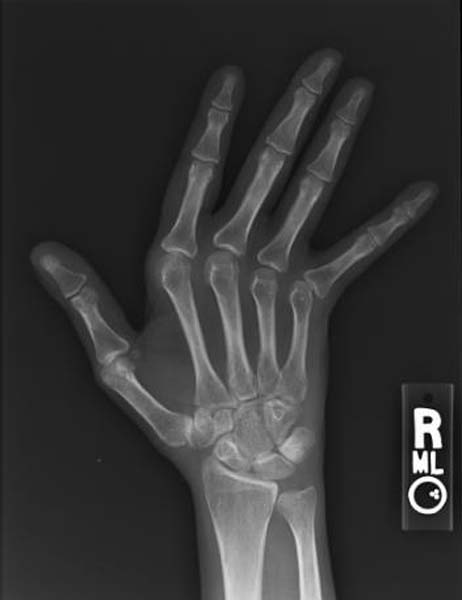

3.2. Hội chứng Jaccoud

– Biến dạng khớp giống viêm khớp dạng thấp.

– Không có tổn thương phá hủy trên X-quang.

– Các ngón tay có thể nắn chỉnh về vị trí ban đầu.

– Đây là dấu hiệu gợi ý lupus quan trọng, dễ bị bỏ sót nếu không thăm khám chuyên sâu.